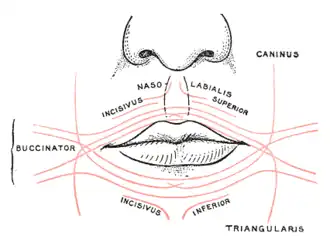

The fibers converge toward the angle of the mouth, where the central fibers intersect each other, those from below being continuous with the upper segment of the orbicularis oris, and those from above with the lower segment; the upper and lower fibers are continued forward into the corresponding lip without decussation.

Scheme showing arrangement of fibers of orbicularis oris

Scheme showing arrangement of fibers of orbicularis oris -